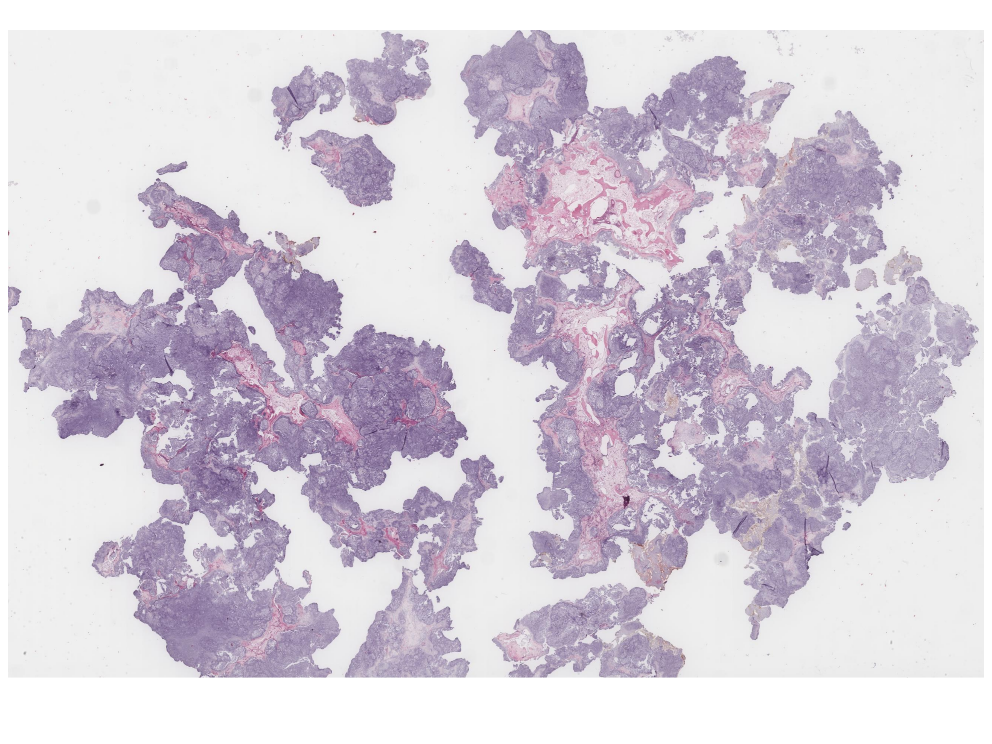

Rhabdomyosarcoma of Bladder